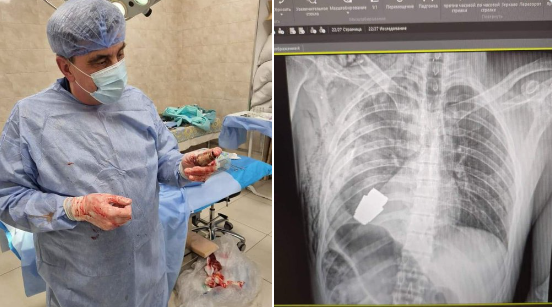

O operacji, którą przeprowadził jeden z najbardziej doświadczonych ukraińskich chirurgów wojskowych - Andrij Werba, wiceminister obrony Ukrainy poinformowała na Twitterze.

Jak podkreśliła Malar, pocisk mógł eksplodować w każdym momencie, dlatego zabieg przeprowadzono bez użycia elektrokoagulacji, czyli metody, w której wykorzystywany jest niewielki przepływ elektryczny.

Operacja przebiegła pomyślnie, ranny żołnierz przechodzi teraz rehabilitację i rekonwalescencję. "Nie każda rana w pobliżu serca jest śmiertelna!" - podkreśliła wiceminister. Opublikowane przez nią fotografie pokazują spory pocisk widoczny na zdjęciu rentgenowskim klatki piersiowej rannego żołnierza i ten sam pocisk wydobyty już przez chirurga. (PAP)